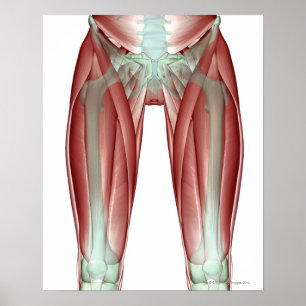

Póster Músculo-esqueleto do membro inferior

Preço27,90 €